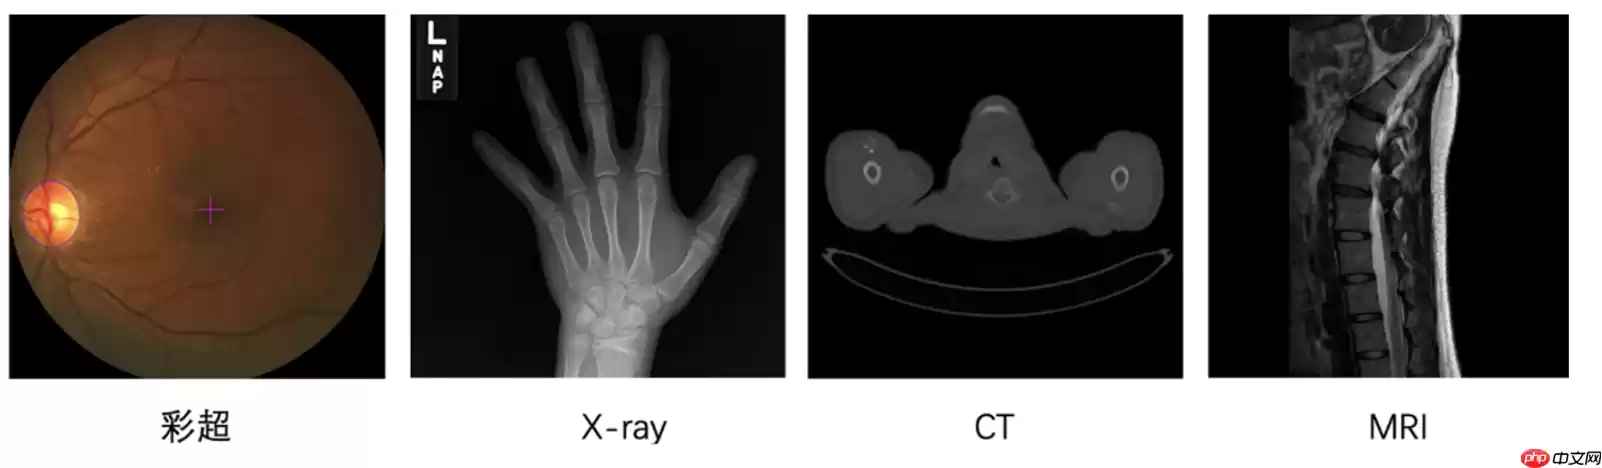

医学影像是临床疾病诊断的重要方式,高效精准的从影像中识别出器官结构或病变,是医学影像学中重要的课题。根据成像原理,医疗影像可以粗略分为两类:

2D成像:一种是在可见光下获取的RGB彩照,如眼底彩照、皮肤彩照等;

3D成像:借助非可见光或其它物理效应,由计算机辅助成像,如CXR/DR(X-Ray),CT,核磁共振(MRI)等。如CT与MRI数据是多个2D切片沿第三个空间维度堆叠而成的;